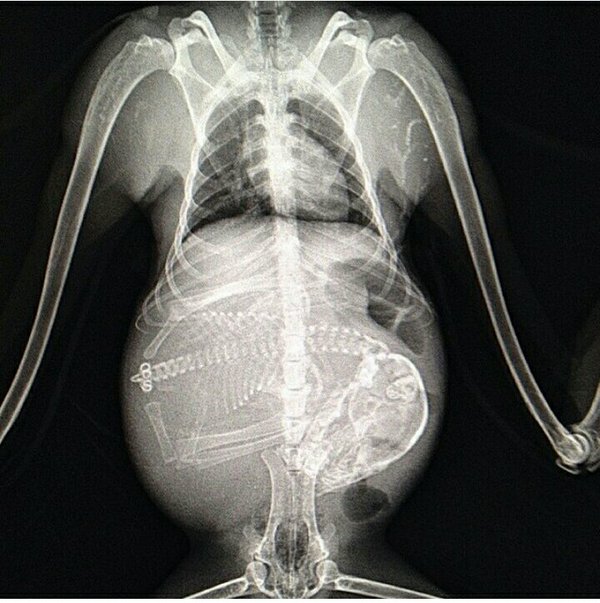

Беременная собака.